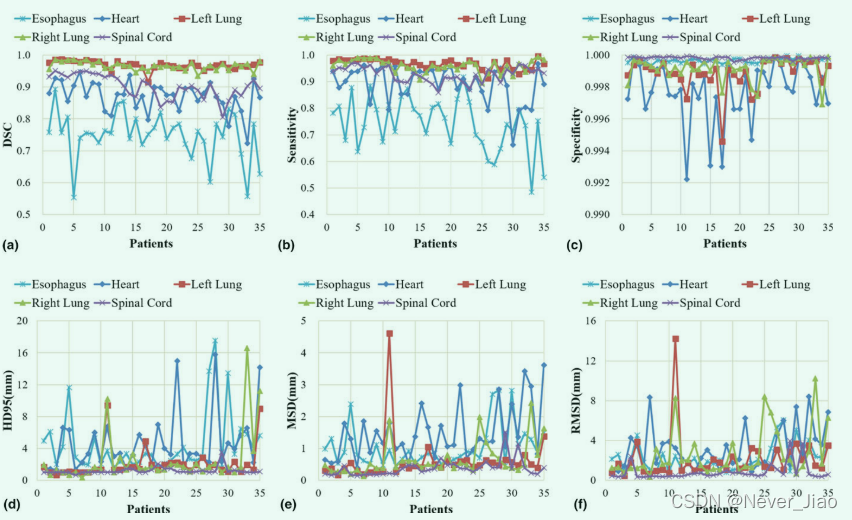

定量评估结果总结在图 5 和表 I 中。图 5 显示了对所有 35 名患者进行计算的六个评估指标——DSC、敏感性、特异性、HD95、MSD 和 RMSD,其平均值和标准差列于表中 I. 如图 5 和表 I 所示,所提出的方法在左肺、右肺和脊髓上实现了优异的分割精度,分别为 0.97、0.97 和 0.90 的平均 DSC,平均 HD95 为 2.07、2.50 和 1.19 毫米,所有平均 MSD 小于 1 毫米。由于图像对比度降低,心脏分割不如肺和脊髓分割简单。定量评估表明,所提出的方法与心脏描绘的基本事实非常吻合。平均DSC为0.87,平均HD95为4.58 mm,平均MSD为1.49 mm。在CT图像上,食管是五个器官中对比度最低的,因此最难描绘。提出的方法在食道分割上获得0.75±0.08 DSC、4.52±3.81 mm HD95和1.05±0.66 mm MSD。灵敏性评估真实的OAR体积与从该方法获得的体积重叠,而特异性量化真实体积之外的重叠部分。该方法的平均分割灵敏度为0.74–0.97,双侧肺最高,食道最低。这五种器官的特性几乎是一致的。五个器官的平均RMSD范围为0.8至3.1 mm。

Fig.5 六个评估指标,(a) Dice相似系数,(b) 灵敏度,© 特异性,(d) 95% Hausdorff 距离,(e) 平均表面距离和 (f) 对 35 名患者的五个风险器官计算的残余均方偏差-。